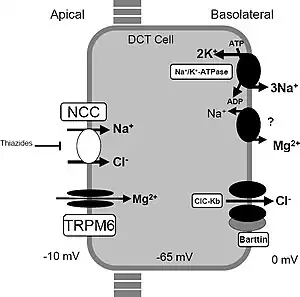

| A model of transport mechanisms in the distal convoluted tubule. Sodium chloride (NaCl) enters the cell via the apical thiazide-sensitive NCC and leaves the cell through the basolateral Cl− channel (ClC-Kb), and the Na+/K+-ATPase. Indicated also are the recently identified magnesium channel TRPM6 in the apical membrane, and a putative Na/Mg exchanger in the basolateral membrane. These transport mechanisms play a role in familial hypokalemia-hypomagnesemia or Gitelman syndrome. | |

Gitelman syndrome (GS) is an autosomal recessive kidney tubule disorder characterized by low blood levels of potassium and magnesium, decreased excretion of calcium in the urine, and elevated blood pH.[1] The disorder is caused by genetic mutations resulting in improper function of the thiazide-sensitive sodium-chloride symporter (SLC12A3, also known as NCC, NCCT, or TSC) located in the distal convoluted tubule of the kidney.[1] The distal convoluted tubule of the kidney plays an important homoestatic role in sodium and chloride absorption as well as of the reabsorption of magnesium and calcium.[2]

Genetic mutations of NCC, lead to loss of function and subsequently, reduced transport of sodium and chloride via NCC. Secondary derangement of calcium, magnesium, and potassium concentrations are caused by secondary effects in the distal tubule and collecting duct. The effect is an electrolyte imbalance similar to that seen with thiazide diuretic therapy (which causes pharmacological inhibition of NCC activity).

Most cases of Gitelman syndrome are linked to inactivating mutations in the SLC12A3 gene, resulting in a loss of function of the thiazide-sensitive sodium-chloride co-transporter (NCCT).[1] This genetic mutation in SLC12A3 is present in 80% of adults with Gitelman syndrome.[1] More than 180 mutations of this transporter protein have been described.[1] This cell membrane protein participates in the control of ion homeostasis at the distal convoluted tubule portion of the nephron. Loss of this transporter also has the indirect effect of increasing calcium reabsorption in a transcellular fashion. This has been suggested to be the result of a putative basolateral Na+/Ca2+ exchanger and apical calcium channel.

When the sodium-chloride cotransporter (NCCT) is inactivated, continued action of the basolateral Na+/K+-ATPase creates a favourable sodium gradient across the basolateral membrane. This increases the reabsorption of divalent cations by secondary active transport. It is currently unknown why calcium reabsorption is increased while magnesium absorption is decreased, often leading to a low level of magnesium in the blood .

A small percentage of Gitelman syndrome cases can be attributed to mutations in the CLCNKB gene. This gene is related to the function of the renal chloride channel CLC-Kb located at the basolateral membrane of cells in the thick ascending limb of the Henle's loop. Genetic variations or mutations in the CLCNKB was initially linked to classic Bartter Syndrome. When mutations are not found within the SLC12A3 gene, screening can be done to rule out involvement of CLCNKB gene.[9]